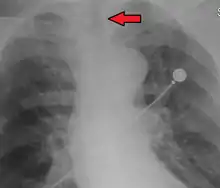

An endotracheal tube in good position on CXR. Arrow marks the tip.

No single method for confirming tracheal tube placement has been shown to be 100% reliable. Accordingly, the use of multiple methods for confirmation of correct tube placement is now widely considered to be the standard of care.[35] Such methods include direct visualization as the tip of the tube passes through the glottis, or indirect visualization of the tracheal tube within the trachea using a device such as a bronchoscope. With a properly positioned tracheal tube, equal bilateral breath sounds will be heard upon listening to the chest with a stethoscope, and no sound upon listening to the area over the stomach. Equal bilateral rise and fall of the chest wall will be evident with ventilatory excursions. A small amount of water vapor will also be evident within the lumen of the tube with each exhalation and there will be no gastric contents in the tracheal tube at any time.[34]

Ideally, at least one of the methods utilized for confirming tracheal tube placement will be a measuring instrument. Waveform capnography has emerged as the gold standard for the confirmation of tube placement within the trachea. Other methods relying on instruments include the use of a colorimetric end-tidal carbon dioxide detector, a self-inflating esophageal bulb, or an esophageal detection device.[36] The distal tip of a properly positioned tracheal tube will be located in the mid-trachea, roughly 2 cm (1 in) above the bifurcation of the carina; this can be confirmed by chest x-ray. If it is inserted too far into the trachea (beyond the carina), the tip of the tracheal tube is likely to be within the right main bronchus—a situation often referred to as a "right mainstem intubation". In this situation, the left lung may be unable to participate in ventilation, which can lead to decreased oxygen content due to ventilation/perfusion mismatch.[37]